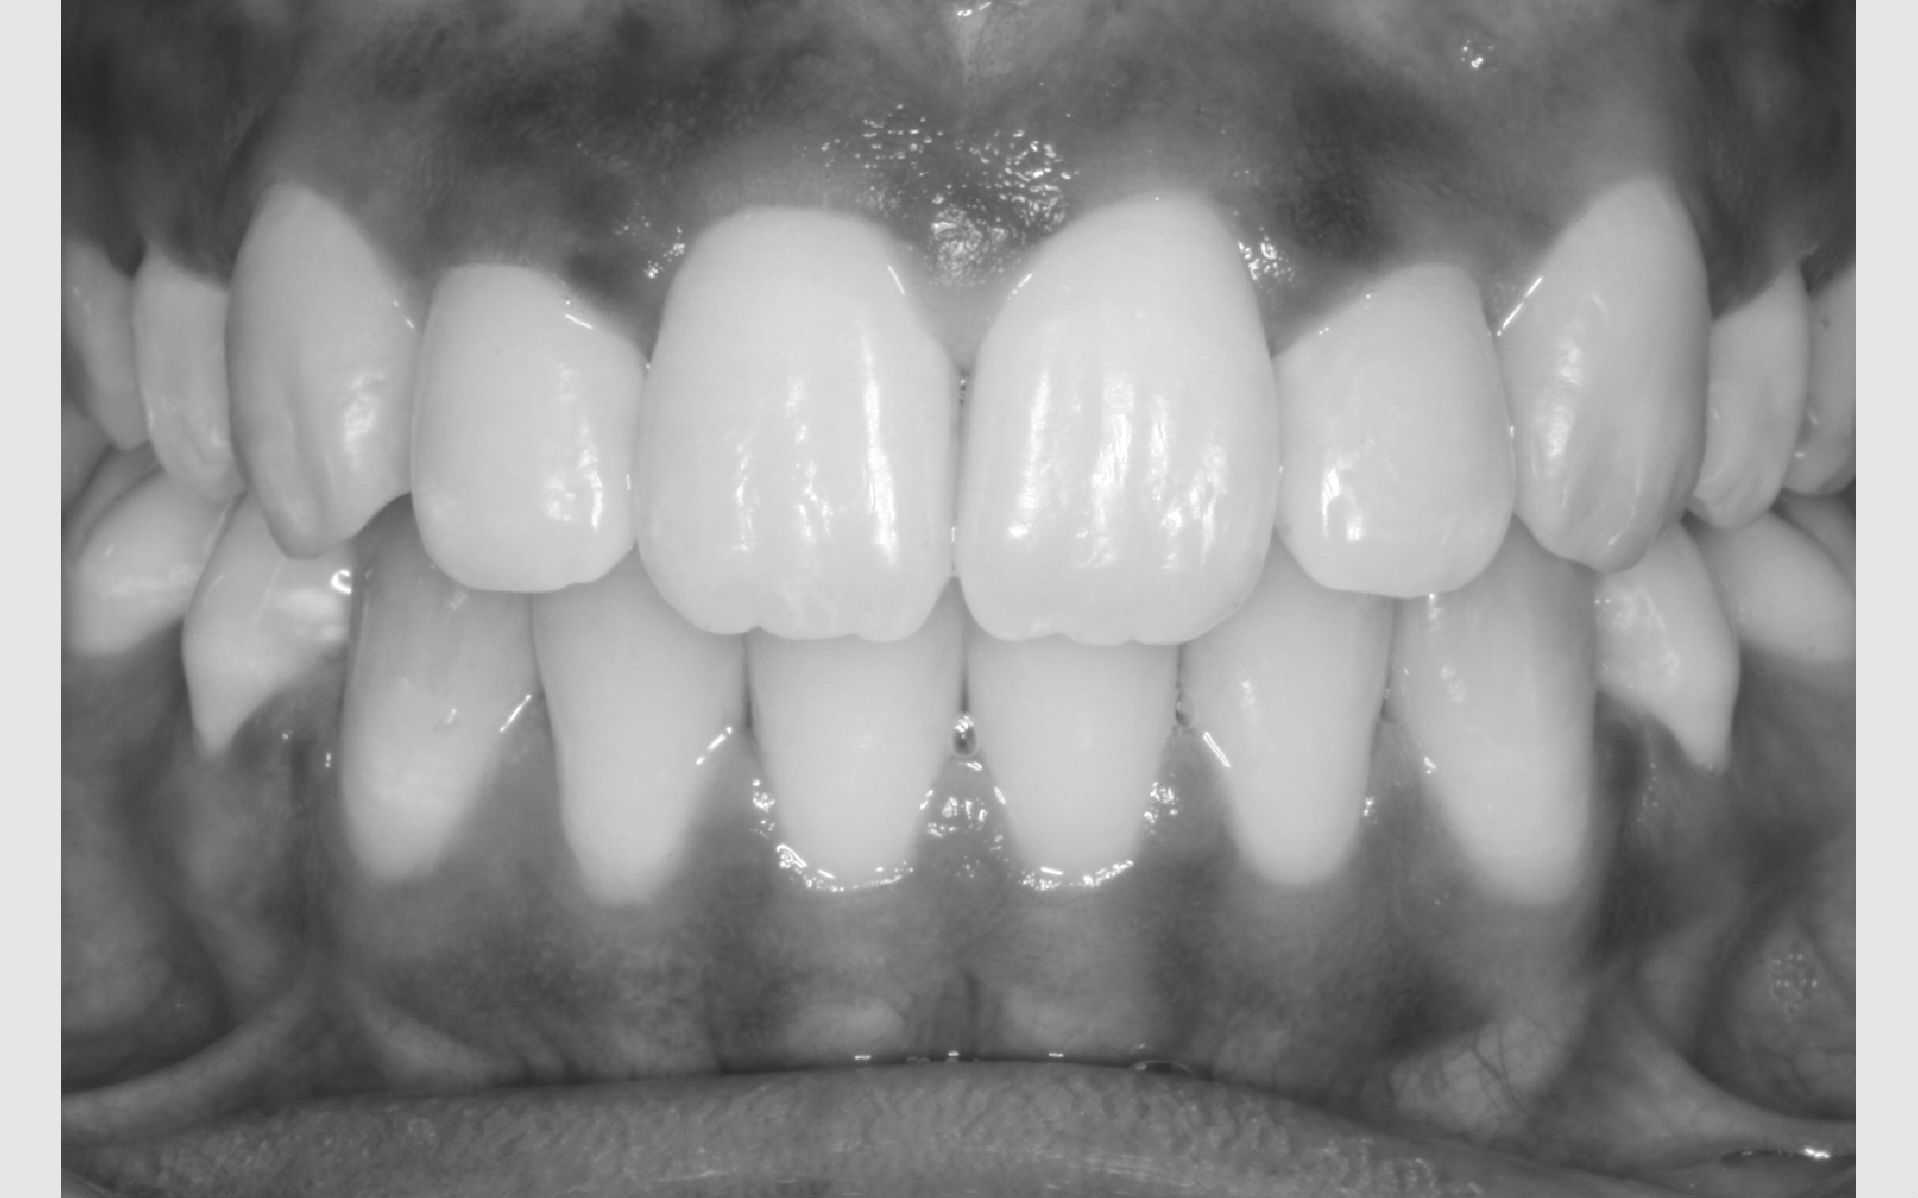

Første gang dit barn besøger Tandreguleringsklinikken, bliver der lavet studiemateriale.

Studiemateriale, består af modeller, fotos og røntgenbilleder af tænder og ansigt. Der bliver også udleveret et helbredsskema, som skal udfyldes på stedet. Det er vigtigt at vide, om jeres barn er sundt og raskt, eller om der er særlige hensyn, vi skal tage - eksempelvis til medicin med videre.

Der bliver taget billeder "udenpå og indeni" samt røntgenbilleder.

Dit barn skal selv holde sine læber til side med en læbeholder, mens tænderne bliver fotograferet. Billederne har følgende formål: